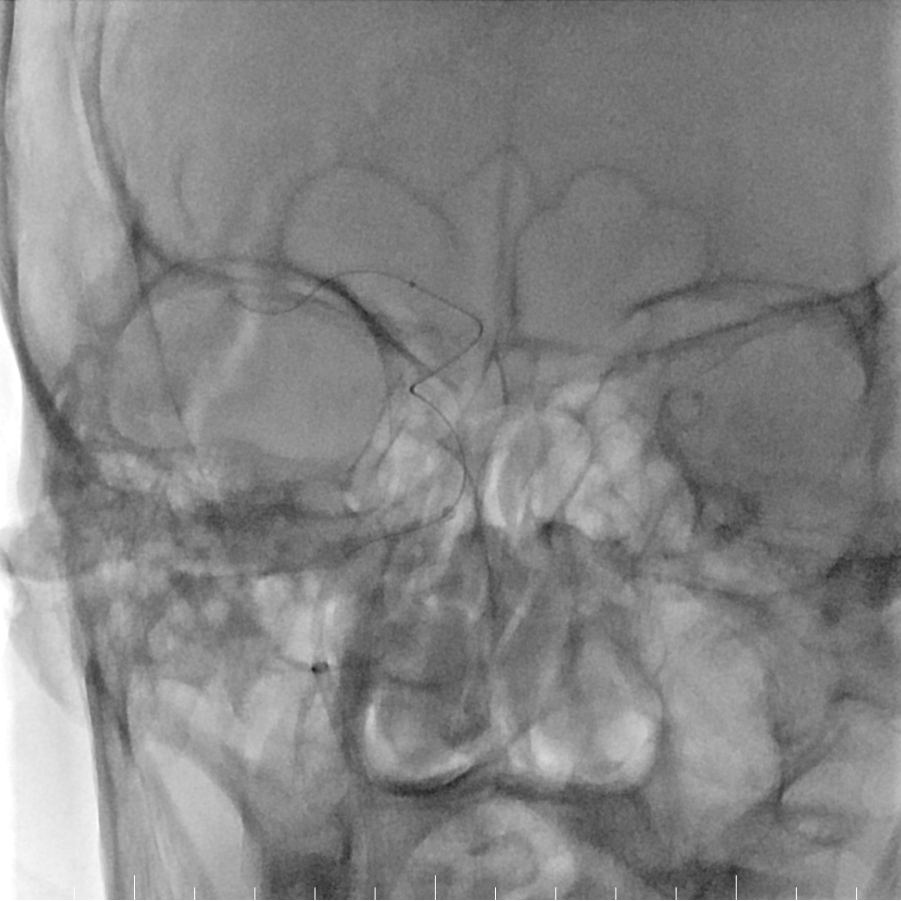

Tarvos微导丝轻松超选,到达M1段。

动脉长鞘怎么置入有励可说|Locaste 088励楷长鞘及Tarvos微导丝在右侧大脑中动脉M2段取栓术中的应用_https://www.jmylbn.com_新闻资讯_第12张

Tarvos微导丝携微导管到位。

支架释放,采用SWIM技术取栓。